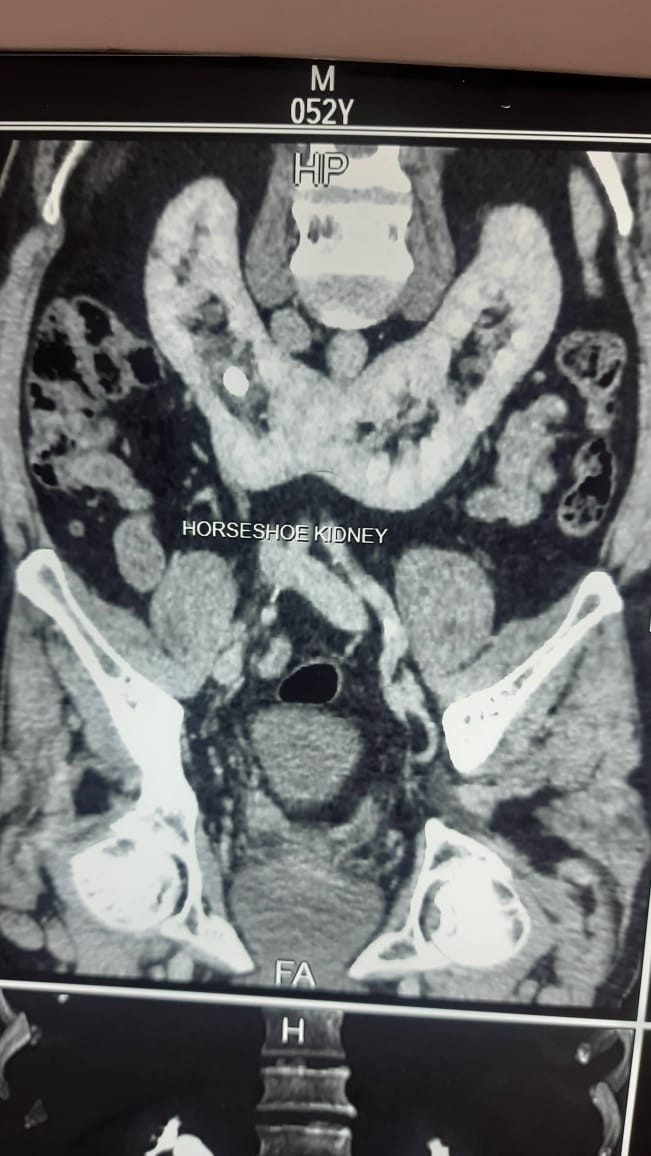

2. Clinical Work at Center